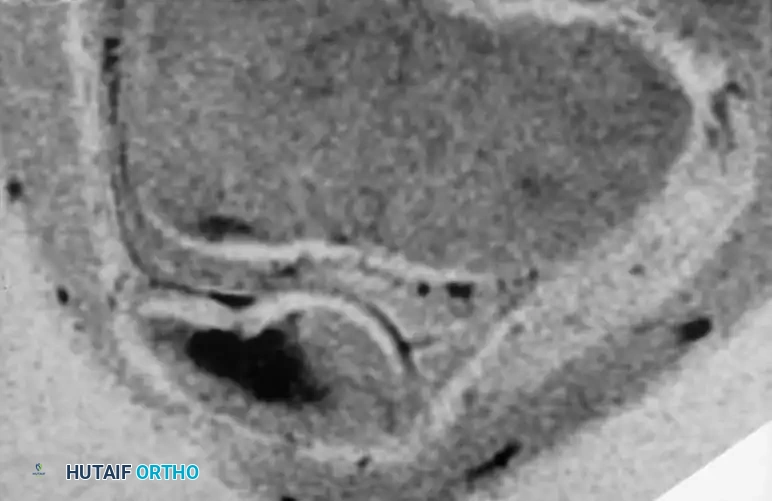

Osteochondritis dissecans (OCD) of the ankle primarily affects the talar dome. The natural history of this lesion in children with open physes is highly favorable compared to adult populations.

Natural History and Imaging

Bauer et al., in a long-term follow-up study (≥ 20 years) of 30 children with ankle osteochondritis, found that only one patient developed severe osteoarthritis. The vast majority experienced complete healing with only minor residual radiographic changes. This is in stark contrast to osteochondritis of the knee, where secondary osteoarthritis is a frequent complication.

Radiographic and MRI evaluation of osteochondral lesions of the talar dome, demonstrating subchondral separation and surrounding edema.